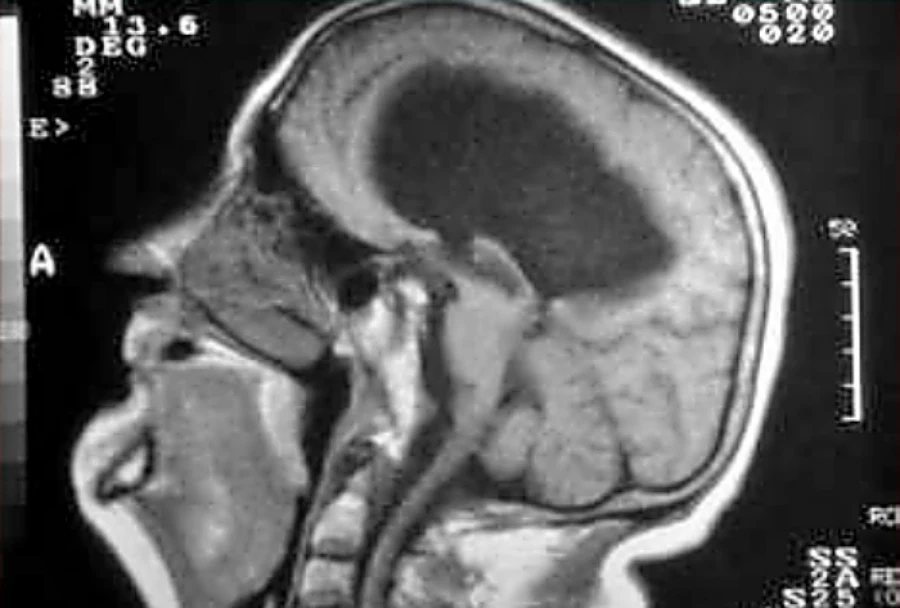

Si ponemos todo este tipo de clasificación juntos, podemos ver que si nos vamos a las hidrocefalias congénitas, como el caso de una estenosis del acueducto, las hidrocefalias congénitas suelen ser:

- Obstructivas

- No comunicantes

- La presión intracraneal es alta

Hidrocefalias Congénitas

Las hidrocefalias congénitas tienen características comunes:

- Son obstructivas

- Son no comunicantes

- Tienen presión intracraneal alta

Un ejemplo típico es la estenosis del acueducto de Silvio, donde la obstrucción impide el paso normal del líquido cefalorraquídeo.